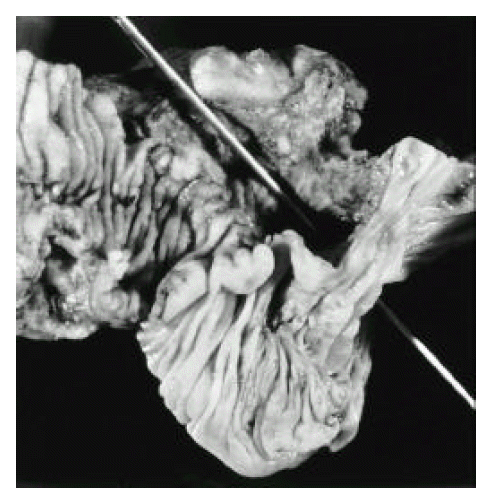

Figure 3.

Gross photograph of this ileocecectomy specimen, revealing cecocecal fistula demonstrated by the probe. Ileocecal valve is destroyed with deep ulceration. The probe is passing throuch the cavitating ulcer in the most proximal cecum on the left upper to more distal non-ulcerated portion of the cecum on the right portion of the photograph.